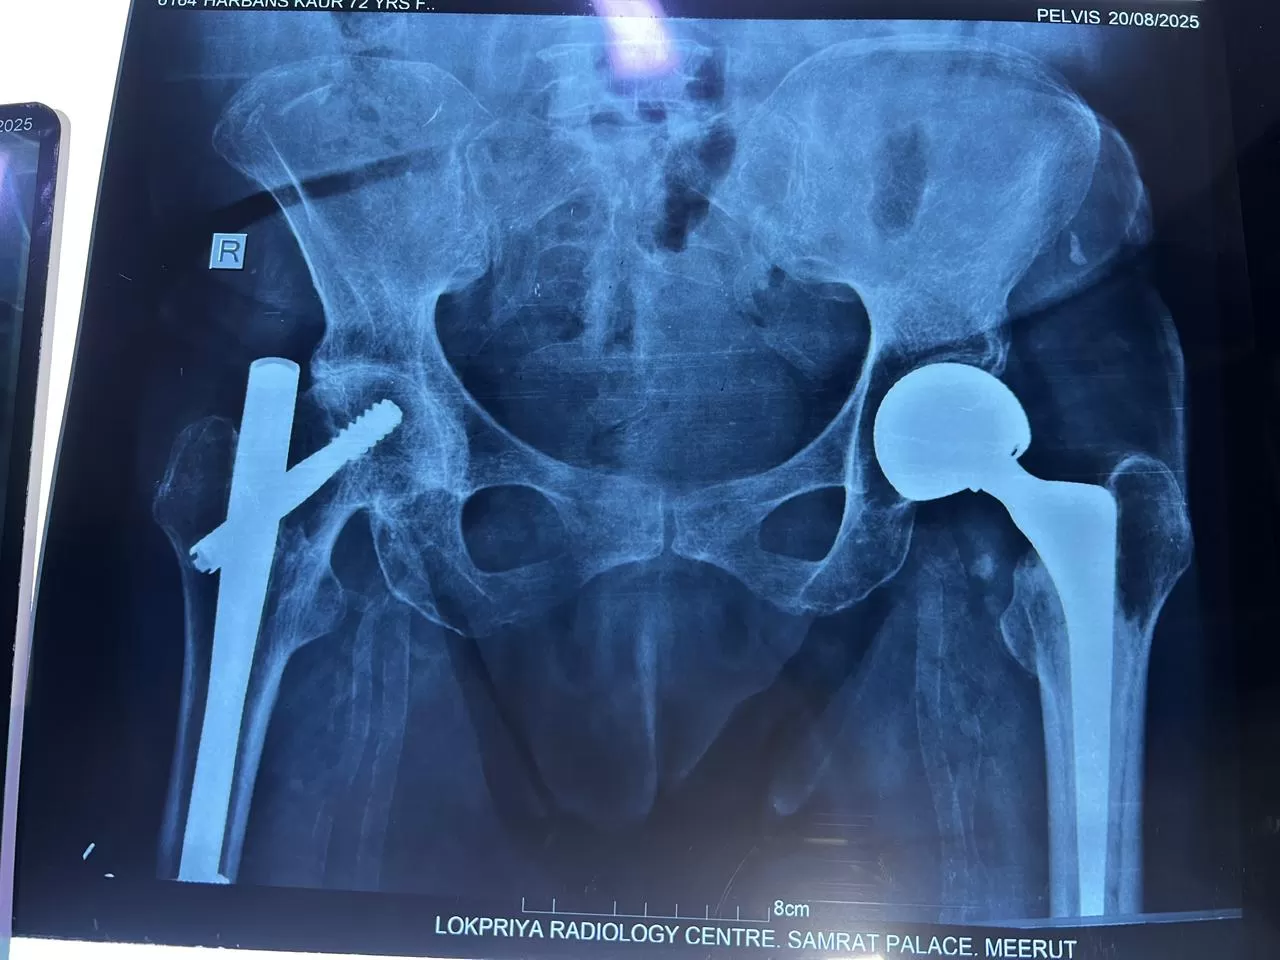

Name: Harbhajan

Date of Operation: 22 October

Age: 70 Years